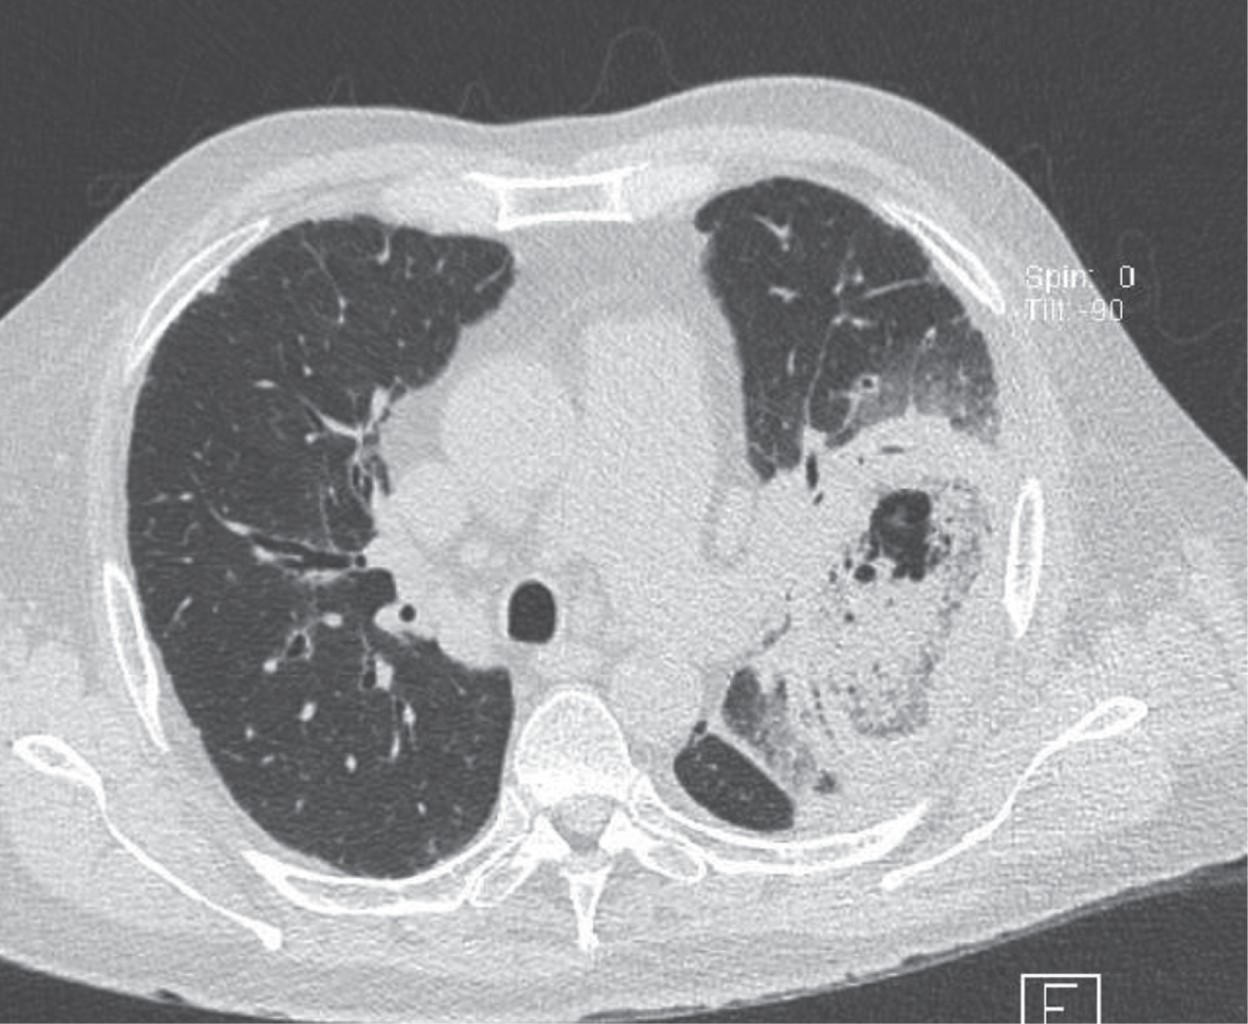

Hombre de 68 años de edad, el cual acude a nuestro hospital en julio 2023 por presentar tos no productiva con expectoración blanquecina, acompañada de disnea de medianos esfuerzos; niega fiebre, sufre pérdida de peso de 6 kg en las últimas semanas. Después de recibir tratamiento antiinfeccioso en el departamento de urgencias durante dos días, con poca mejoría, ingresó a neumología para protocolo diagnóstico y terapéutico; se tomó radiografía de tórax al momento de su ingreso (Figura 1); se programó estudio tomográfico de tórax (Figura 2), donde se encontró masa cavitada bien definida dentro del lóbulo superior izquierdo, con el signo de la media luna de aire. Por sospecha diagnóstica de tuberculosis pulmonar, se solicitó estudio de broncoscopia para lavado broncoalveolar y prueba de bacilos ácido-alcohol resistentes (BAAR), cultivo de micobacterias y de hongos, así como de bacterias. Durante el estudio con fibrobroncoscopia se observó una masa exofítica blanquecina en la pared anterior segmento S3 izquierdo, por lo que se decidió toma de biopsia y de muestras (Figura 3); posteriormente, mediante estudio histopatológico, se realizó el diagnóstico de mucormicosis y, por cultivo, mucormicosis Absidia. Se inició manejo con anfotericina B; durante los primeros tres días de iniciado el tratamiento, el paciente aumenta requerimiento de oxígeno, se solicita nueva radiografía de tórax; llega a mascarilla reservorio 15 litros con saturación de 90% con taquipnea, frecuencia respiratoria 30 por minuto, con disociación toracoabdominal, por lo que se decide manejo avanzado de la vía aérea. Fallece por choque séptico en sus primeras 12 horas de estancia en terapia intensiva respiratoria.

Las manifestaciones radiológicas de la mucormicosis pulmonar son en su mayoría inespecíficas; más del 80% de los pacientes muestran resultados anormales en las radiografías de tórax.11 Los hallazgos pueden incluir consolidación, cavitación, el signo de la media luna de aire, el signo del halo, el signo del halo invertido, nódulos o masas pulmonares múltiples o solitarias, fístulas broncopleurales, pseudoaneurismas de la arteria pulmonar, linfadenopatía y derrame pleural. La cavitación se observa en hasta 40% de los casos, aunque el signo de la media luna de aire es poco común. La tomografía computarizada (TC) de alta resolución puede ser más sensible para detectar la enfermedad y puede encontrar evidencia de la infección antes que las radiografías de tórax convencionales. El pulmón derecho se ve afectado con mayor frecuencia que el izquierdo, y hay una predilección por la afectación de los lóbulos superiores, aunque la razón detrás de esto se desconoce. El presente caso reportó una lesión en el lóbulo superior derecho, al igual que la mayoría de los casos en la literatura.11